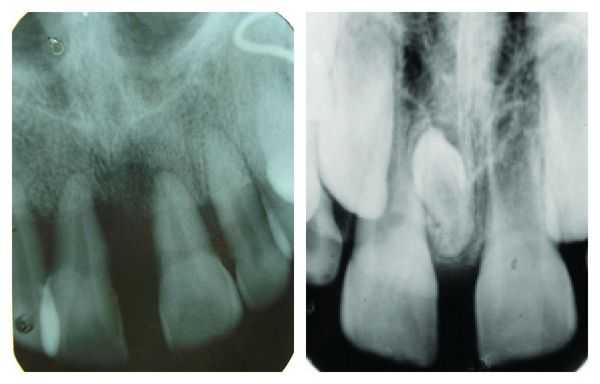

Наличие у пациента диастемы выявляется в ходе визуального осмотра полости рта. Тем не менее, для уточнения причин и вида диастемы требуется проведение ряда дополнительных диагностических процедур: определения прикуса, прицельной рентгенографии, ортопантомографии, снятия слепков, изготовления и изучения диагностических моделей челюстей. При анализе данных учитывается положение, форма, наклон резцов и корней; состояние уздечек; величина межзубного промежутка и симметричность диастемы; характер прикуса, наличие ретинированных зубов и т. д.

Прицельная рентгенография выполняется, чтобы определить расположение корней и установить тип диастемы.

Ортопантомограмма позволяет оценить зубочелюстную систему пациента, увидеть аномалии и отклонения [13] .

Снятие слепков и изготовление гипсовой модели челюсти помогает не только выявить диастему и определить её тип, но и сделать наиболее подходящие и комфортные брекеты или пластины для дальнейшего лечения.

В ходе диагностики выясняются следующие параметры конкретного пациента: стадия развития корней зубов, состояние уздечки, расположение резцов и их форма, степень развития передних резцов, прикус, симметричность/асимметричность промежутка, ширина промежутка. По результатам обследований составляется план лечения.

Диагностика трем

Диагностика трем включает анализ данных физикального обследования, результатов антропометрических измерений и рентгенографии. В ходе обследования пациентов с тремой врач-стоматолог может выявить отсутствие зачатков, неправильное положение (дистопию) или задержку прорезывания одного или нескольких постоянных комплектных зубов. В случае 1 подкласса дистального прикуса тремы диагностируют между протрузионно наклоненными верхними резцами, при мезиальной окклюзии промежутки между зубами выявляют на нижней челюсти.

Для установления истинной причины тремы в ходе антропометрического исследования определяют соответствие размеров зубов длине зубоальвеолярной дуги. Мезиодистальные размеры коронок сопоставляют со среднестатистическими параметрами. Если значения ниже нормы, диагностируют микродентию. Также об индивидуальной микродентии говорят при значении дентофациального индекса меньше 22%. Если тремы являются одним из признаков патологии прикуса, обнаруживают увеличение базиса верхней или нижней челюсти. У пациентов с тремами и протрузией передних зубов по методу Герлаха обнаруживают диспропорциональность в размерах бокового и переднего участков, измерения по Коркхаузу свидетельствуют об удлинении переднего отрезка.

С помощью рентгенографического исследования определяют наличие зачатков всех комплектных зубов, их положение. Телерентгенография показана пациентам с тремами, появившимися вследствие аномалии прикуса. Результаты исследования дают информацию о типе роста челюстей, наличии скелетной или зубоальвеолярной патологии, что имеет большое значение при составлении рационального плана лечения. Обследование пациента с тремами проводит стоматолог-ортодонт.